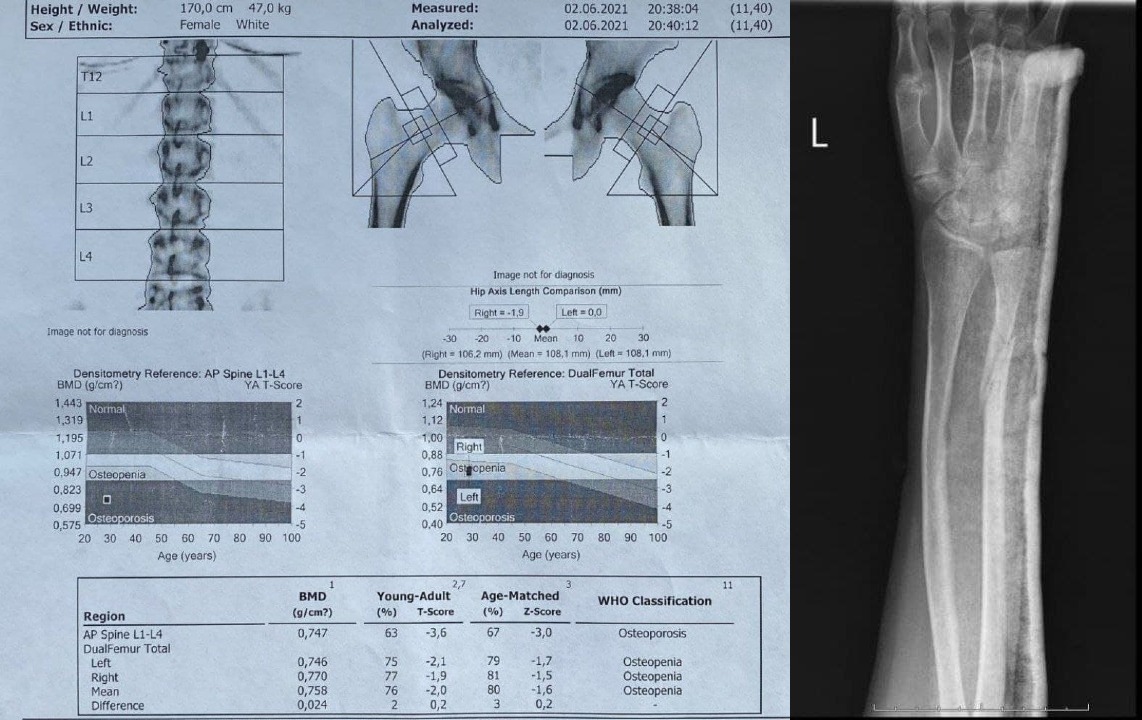

Интересно последнее исследование минеральной плотности костной ткани от 02.06.21.

Т критерий : AP spine L1-L4 - 3.6, femur left -2.1, femur right -1.9, mean -2.